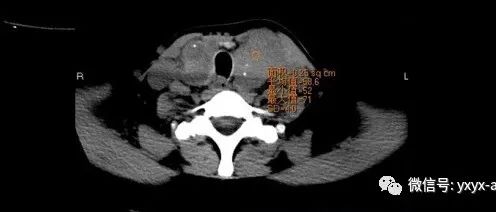

医学影像  yxyx-app  医学影像APP,打造伴随医生快速成长的影像学习社区。与影像园(Xctmr.com)一起提供最全面的影像案例库、基础(解剖、病理、影像诊断)知识、影像技术及考题等,为医生提供最佳的医学影像参考。【所属科室】内分泌科【基本资料】患者,女,63岁【主诉】发现双侧颈部包块8年余,呼吸急促不畅2天【体格检查】左侧颈部可触及直径5cm包块,右侧颈部可触及3cm包块,质韧,活动度可,压痛(-),包块随吞咽上下活动,颈部未触及肿大淋巴结。...